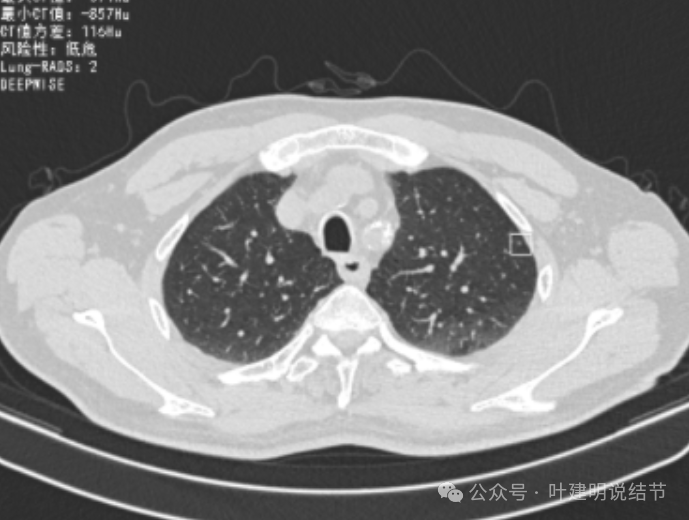

增强纵隔窗见病灶内部的密度好像低于周围区域,像坏死。

邻近胸膜无牵拉,灶内有低密度区,局部有点状液性密度。邻近胸膜较为广泛的增厚或胸膜反应。

病灶与胸膜接触面宽,病灶内部密度较低。